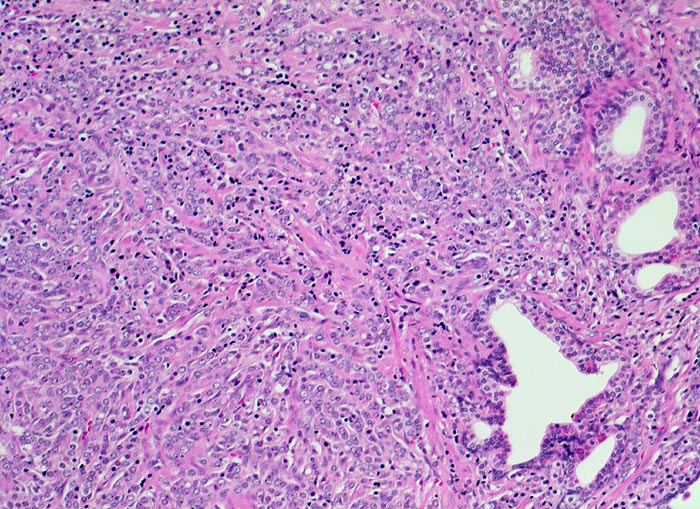

Neben einzelnen benignen grossen Prostatadrüsen findet sich ein diffuses Infiltrat schlecht geformter, sehr kleiner, dichtliegender maligner Drüsen und einzeln liegender Tumorzellen mit grossen Zellkernen und wenig Zytoplasma.

Schlecht geformte, miteinander fusionierte Karzinomdrüsen, die sich infiltrativ zwischen normalen Drüsen ausbreiten entsprechen einem Gleason Grad 4. Dissolut liegende Tumoreinzelzellen oder Tumorzellstränge, die keine drüsigen Strukturen erkennen lassen, entsprechen einem Gleason Grad 5 (überwiegendes Muster im vorliegenden Bildausschnitt).